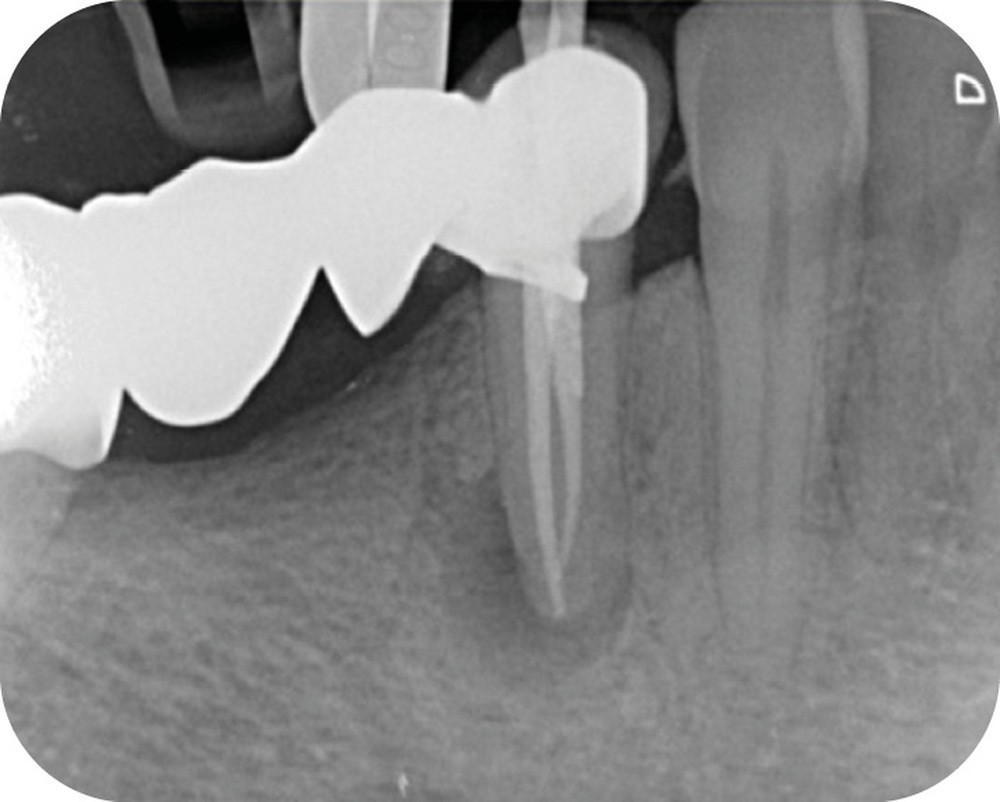

La cavité d’accès endodontique était alors traditionnellement réalisée en se figurant les axes de la racine et du bridge (fig. 2). Cette aptitude à s’orienter dans l’espace n’est cependant pas aisée, et différents outils numériques offrent aujourd’hui la possibilité de dessiner la trajectoire suspectée du canal sur les coupes de l’examen Cone Beam et d’aider le praticien à planifier son futur geste thérapeutique (fig. 3, 4). Après pose du champ opératoire, une voie d’accès est ainsi réalisée à travers le bridge en reportant les mesures de la planification 3D (fig. 5). Le tenon est déposé par vibration avec un insert ultrasonore puis la lecture des teintes dentinaires sous microscope permet d’objectiver la présence d’un canal supplémentaire non traité (fig. 6). Les surplombs dentinaires sont supprimés avec un insert ET18D (Actéon) et les entrées canalaires relocalisées avec une lime rotative d’évasement coronaire.

La mise en forme canalaire à travers un bridge impose des contraintes instrumentales importantes, et nécessite une analyse préopératoire minutieuse. Ici, nous avons eu recours à des limes de pré-élargissement mécanisé afin de sécuriser la trajectoire canalaire (fig. 7). Une préparation corono-apicale jusqu’à une finition apicale 25-6 % a ensuite été choisie afin d’optimiser le flux d’irrigant dans le tiers apical. À la suite de l’ajustage des maîtres cônes et d’un protocole d’irrigation finale (EDTA & NaOCl), une obturation selon la technique de condensation verticale à chaud est réalisée, puis la patiente est revue pour une restauration composite de la face occlusale (fig. 8, 9). Le contrôle à six mois révèle la disparition de la symptomatologie ainsi que des signes radiologiques de cicatrisation apicale (fig. 10).